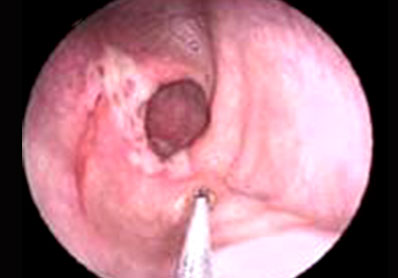

是一种慢性、反复性、多发性以结肠、乙状结肠和直肠为发病部位。指直肠结肠因各种致病原因导致肠道的炎性水肿,溃疡、出血病变。症状为左下腹疼、腹泻、里急后重、时便下沾液、便秘或泄泻交替性发生、时好时坏,缠绵下断、反复发作。